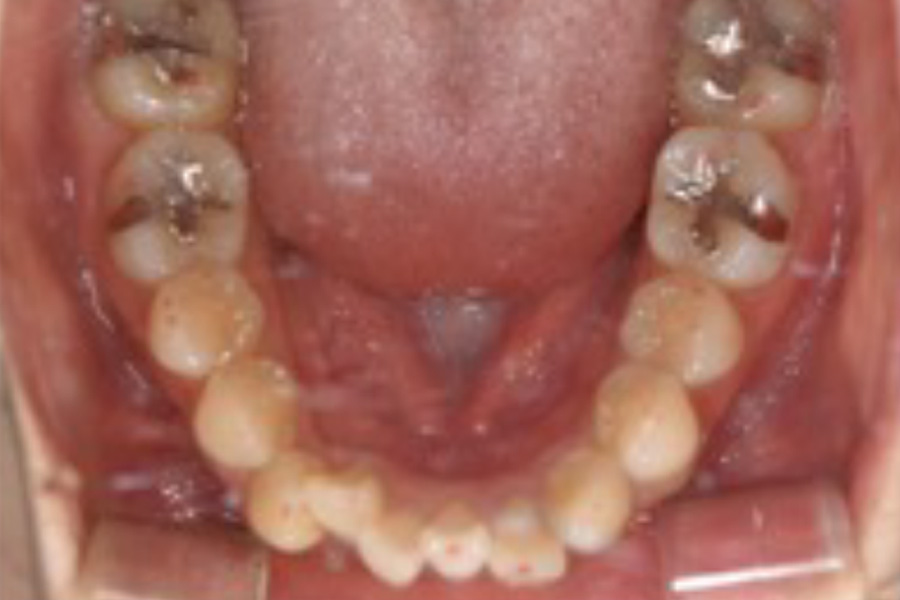

治療前

主訴 右上が気になる。下顎の歯並びを治したい。

期間 3年

費用 マウスピース矯正

980,000円(税込)(2024年時点)

治療内容 目立ちにくいマウスピース矯正(非抜歯矯正)

歯と歯の間に隙間をつくることにより、歯列弓を広げながら治療を行いました。